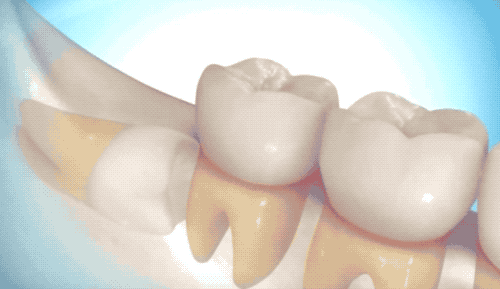

首先介紹相對(duì)簡(jiǎn)單的拔除,雖然沒(méi)有完全長(zhǎng)出來(lái),但是沒(méi)有長(zhǎng)歪的那類(lèi)智齒。

切開(kāi)牙床,翻開(kāi)牙肉,露出白白的牙槽骨和智齒。很多人白的牙齒可能就是沒(méi)有完全萌發(fā)的智齒了…

看到里頭白白的,豎著長(zhǎng)還挺乖的智齒,用牙挺直接撬出來(lái)即可。有時(shí)候醫(yī)生也會(huì)拿錘子敲一敲,用鉗子給揪下來(lái)。